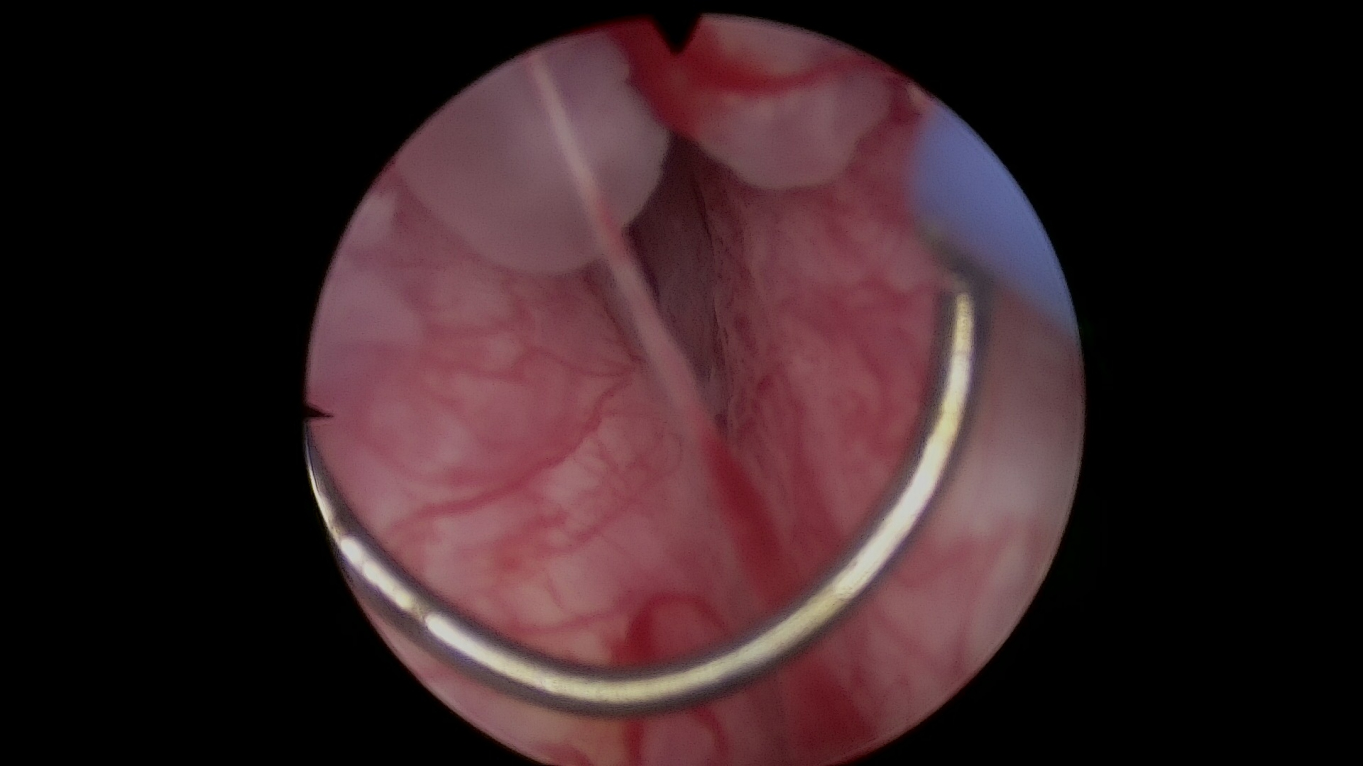

1.超高清成像系统、输尿管镜、膀胱镜等

3.钬激光碎石系统

泌尿系统结石的钬激光碎石